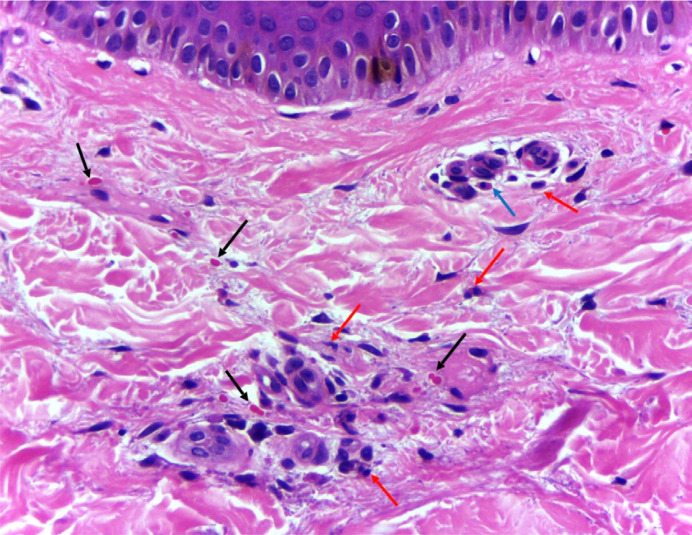

目前,已知至少有22种巴尔通体可引起人类疾病,其中以亨塞拉巴尔通体为主要种类。在与巴尔通体病相关的临床表现中,皮肤血管炎是罕见的,但它可能是严重的。我们报告一名9岁儿童的病例,他以颈部淋巴结病、关节炎、附睾炎和皮肤血管炎为全身性巴尔通体病的临床表现,使用物种特异性常规聚合酶链反应(PCR)技术在血液和皮肤片段中检测到亨selb阳性。由巴尔通体引起的血管炎是由于细菌的内皮性而发生的,并且可以通过抗中性粒细胞胞浆抗体(ANCA)阳性来模拟全身性血管炎。此外,我们只发现一篇关于附睾炎与母鸡乙虫感染相关的报道,关节炎也被认为是感染的一种不寻常的表现。本病例强调,当出现紫癜、皮肤血管炎、关节炎或附睾炎时,需要在鉴别诊断中考虑巴尔通体病。

Currently, at least 22 species of Bartonella are known to cause diseases in humans, with Bartonella henselae being the main one. Among the clinical manifestations associated with bartonellosis, cutaneous vasculitis is rare, but it can be severe. We report the case of a 9-year-old child who presented with cervical lymphadenopathy, arthritis, epididymitis, and cutaneous vasculitis as clinical manifestations of systemic bartonellosis, with positive detection of B. henselae in blood and skin fragment using species-specific conventional polymerase chain reaction (PCR) techniques. Vasculitis caused by Bartonella spp. occurs due to the endothelial tropism of the bacteria and can mimic systemic vasculitis with positive anti-neutrophil cytoplasmic antibodies (ANCA). Furthermore, we found just one previous report about epididymitis related to B. henselae infection, and arthritis is also considered an unusual manifestation of the infection. This case emphasizes the need to consider bartonellosis among differential diagnoses when faced with presentations of purpura, cutaneous vasculitis, arthritis, or epididymitis.